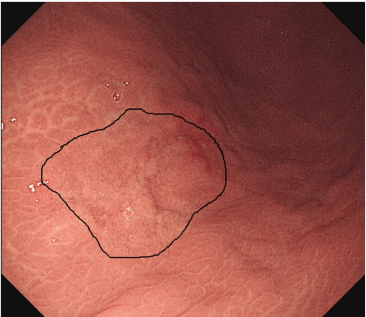

林相宏医生分享胃癌患者病例及胃镜图片:

▲胃癌患者胃镜发生部位。